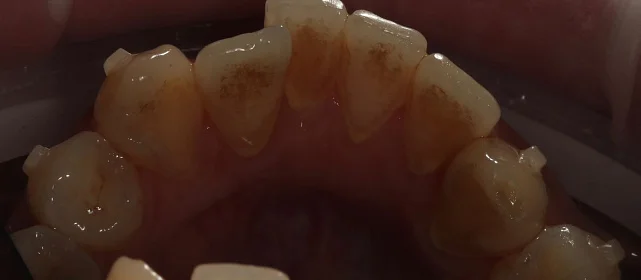

КЛКТ, интраоральное сканирование, пародонтологическое обследование. Подвижности зубов нет, глубина зондирования — в пределах нормы.

Убыль кости — начальная, не превышает 1/4 длины корня.

рецессия десны в области нижних резцов, старые композитные пломбы на боковых зубах.